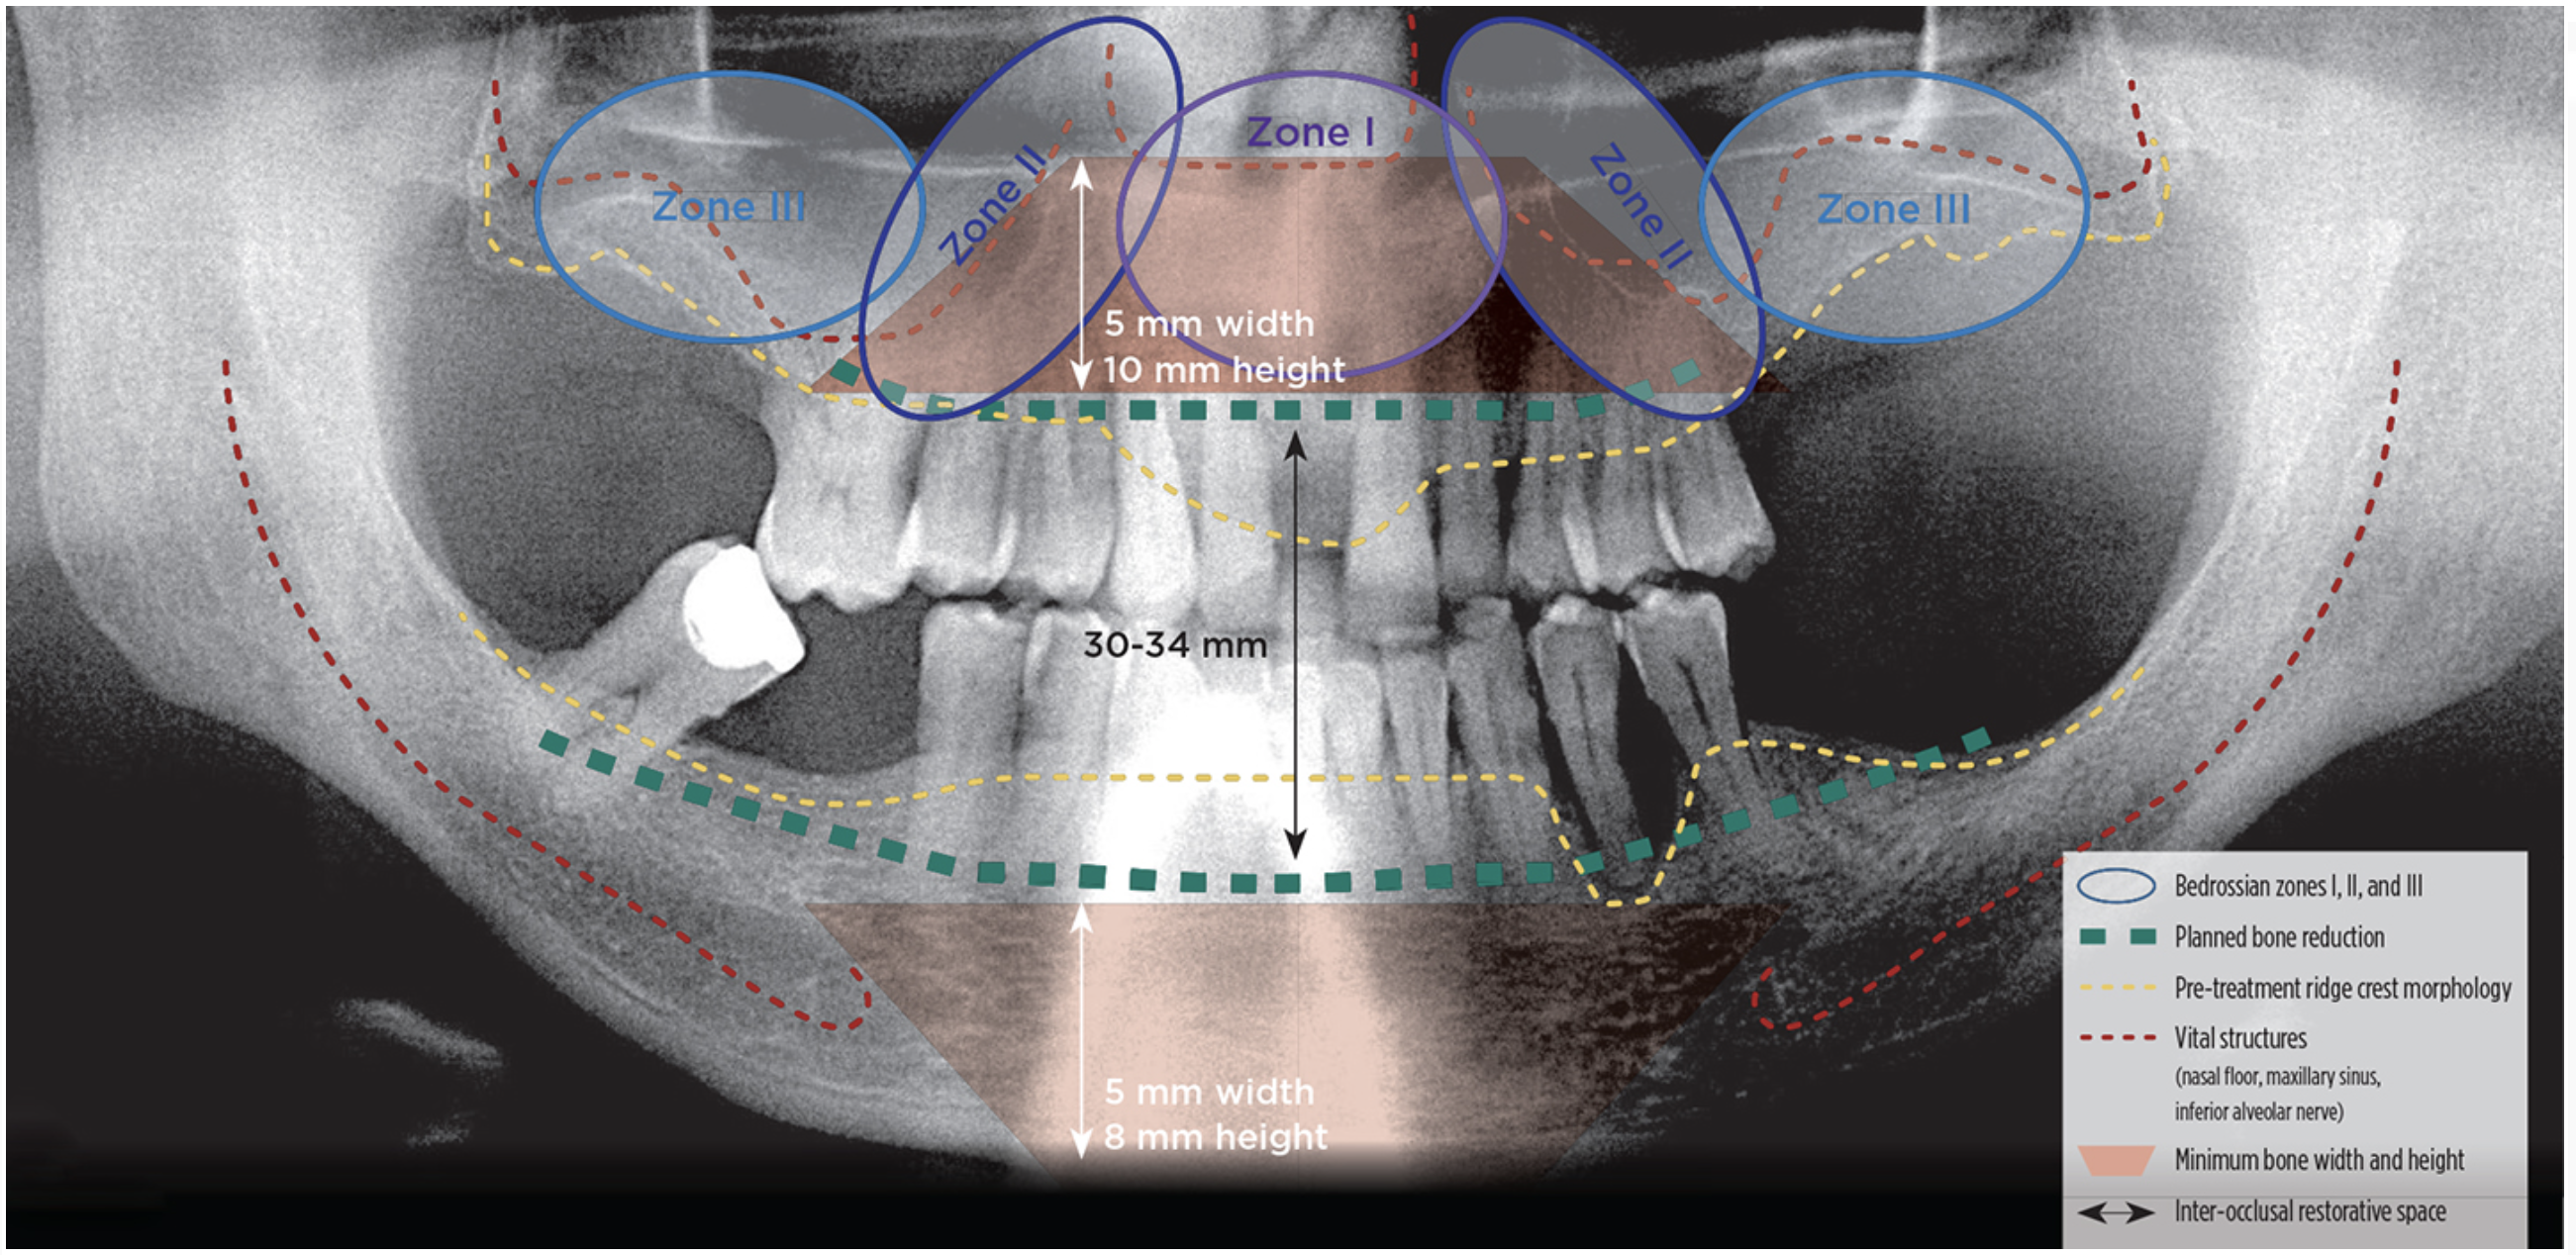

Once the surgeon and the restorative dentist have consulted with the patient and performed a pre-treatment patient evaluation, interdisciplinary treatment planning to identify treatment options for the patient’s dental rehabilitation is completed. The surgeon should have completed and documented a dentofacial and intraoral patient evaluation as well as a radiographic diagnosis and treatment planning survey using cone beam computed tomography (CBCT) (Figure 1) to explore possible treatment options from a surgical perspective. After review of this information, the restorative dentist performs model-based diagnosis and treatment planning. The clinicians jointly review the surgical and restorative treatment planning information and select the treatment option that can be strongly recommended, as well as viable alternatives, for patient education and case presentation.

Fig 1. Radiographic diagnosis and treatment planning survey.

Figure 1

Radiographic Diagnosis and Treatment Planning Survey

• Presence of adequate bone in Bedrossian zones I (pre-maxilla) and II (bicuspid region)

• Location of vital structures, mental nerve, and maxillary sinus

• Presence of composite ridge defects (ridge defect with missing hard and soft tissues)

• Inter-arch space measured between maxillary and mandibular ridge crests at patient’s VDO

• Estimated need for bone reduction to create required inter-occlusal restorative space

• Alveolar ridge width ≥ 5 mm and height ≥ 8 mm in the anterior mandible

• Alveolar ridge width ≥ 5 mm and height ≥ 10 mm in the anterior maxilla

• Bone density classification at primary and backup implant sites

• Verify adequate medullary bone volume for biologic integration at implant sites

• Absence of sinus pathology and patent osteomeatal complex